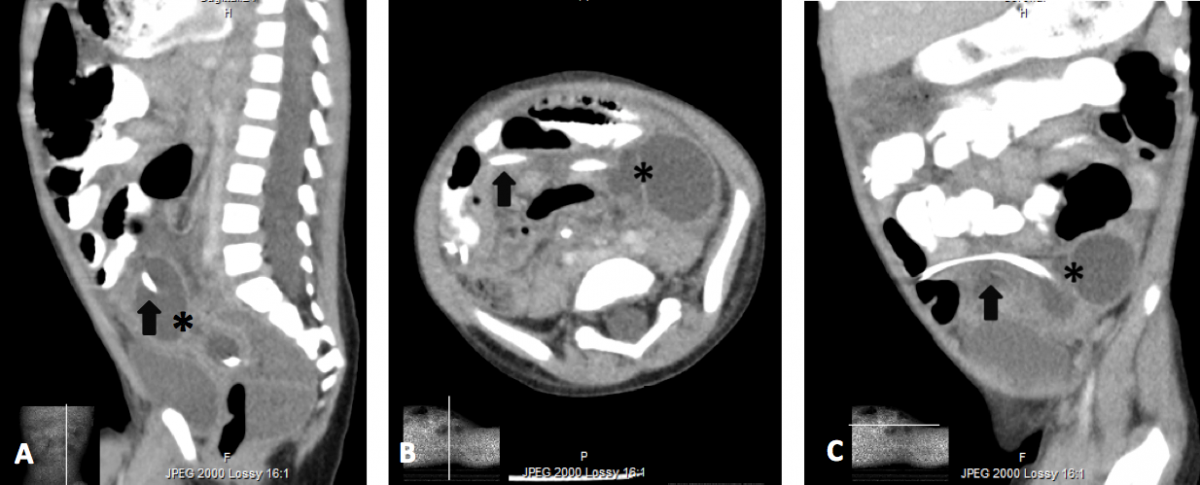

These findings, along with the reported persistent fever and weight loss, prompted concern for occult intra-abdominal abscess or malignancy. As such, a computed tomography (CT) scan with contrast of the abdomen and pelvis was obtained, revealing an organized, rim-enhancing fluid collection surrounding the distal shunt tip in the lower left abdomen, just anterior to the L4 vertebral body; this was compatible with cerebrospinal fluid (CSF) pseudocyst (Figure 2). The patient was then transferred to a tertiary-care facility for anticipated externalization.

Figure 2. Sagittal (a), axial (b), and coronal (c) contrast-enhanced CT images demonstrating the distal VP shunt catheter tip (arrow) and CSF pseudocyst (*).